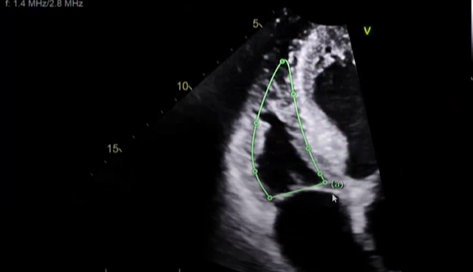

Correctly measure a RV end diastolic for FAC% (area)

Correctly measure RV end systolic for FAC% (area)

what measurement is this

this will be for FAC% but of the RV but at end-systole you want it at the smallest dimension but before the leaflets pop open

this will be for our RV systolic area, make sure when you trace bringing it all the way up to the RV apex this will be RV systolic area